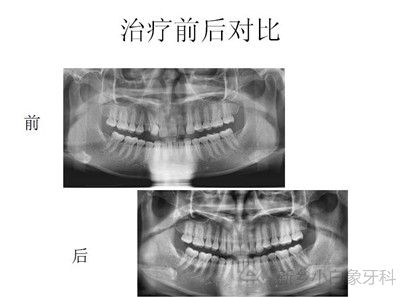

下图为治疗前后图片资料: